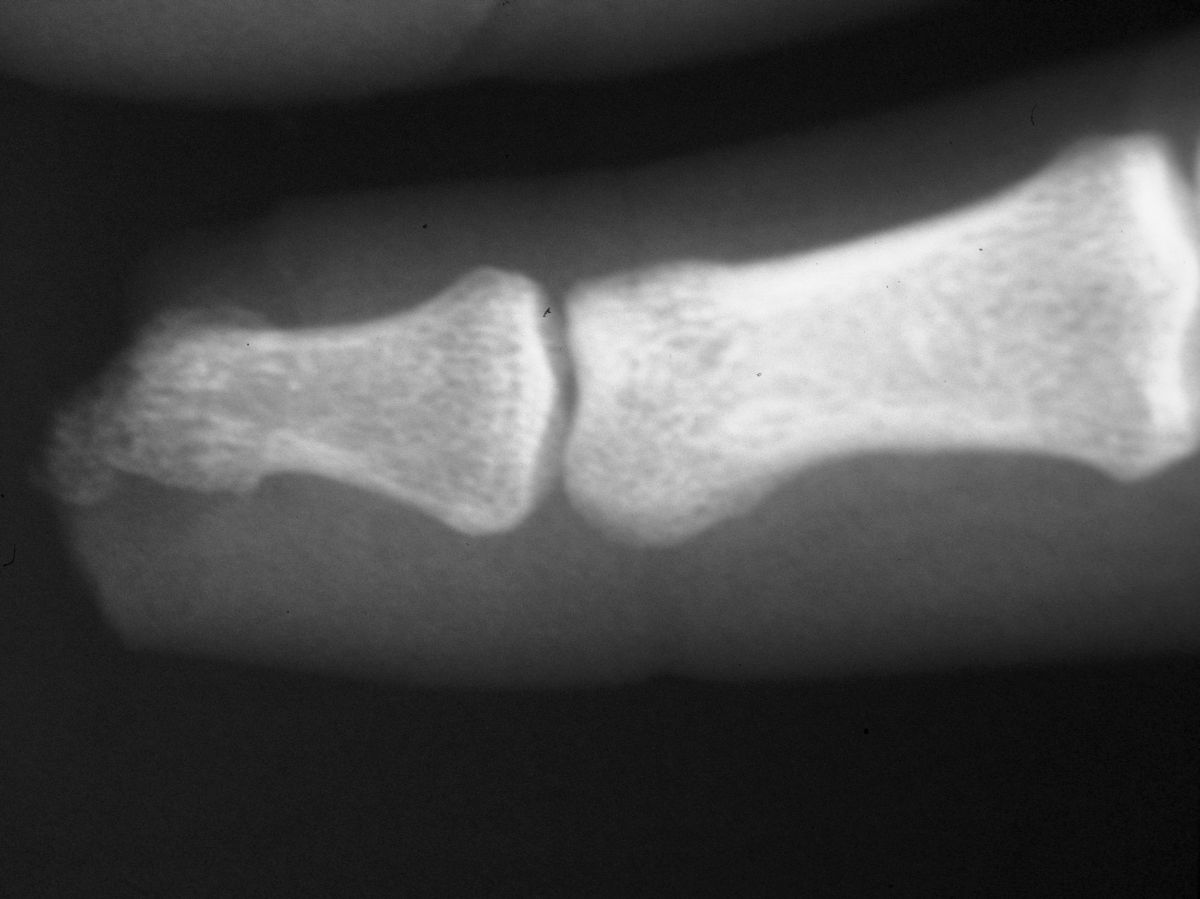

| Case

4. A dog bit off this young man's index fingertip. Although the PA Xray looks as though the bone was kept, additional views show an amputation through the tuft. |